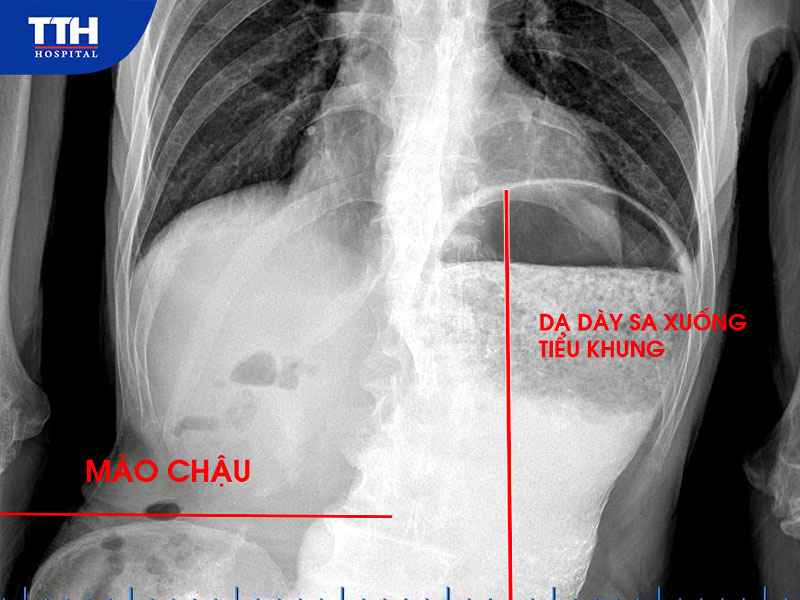

• Chụp dạ dày cản quang ghi nhận dạ dày giãn lớn, sa thấp xuống dưới mào chậu, kéo dài đến tiểu khung